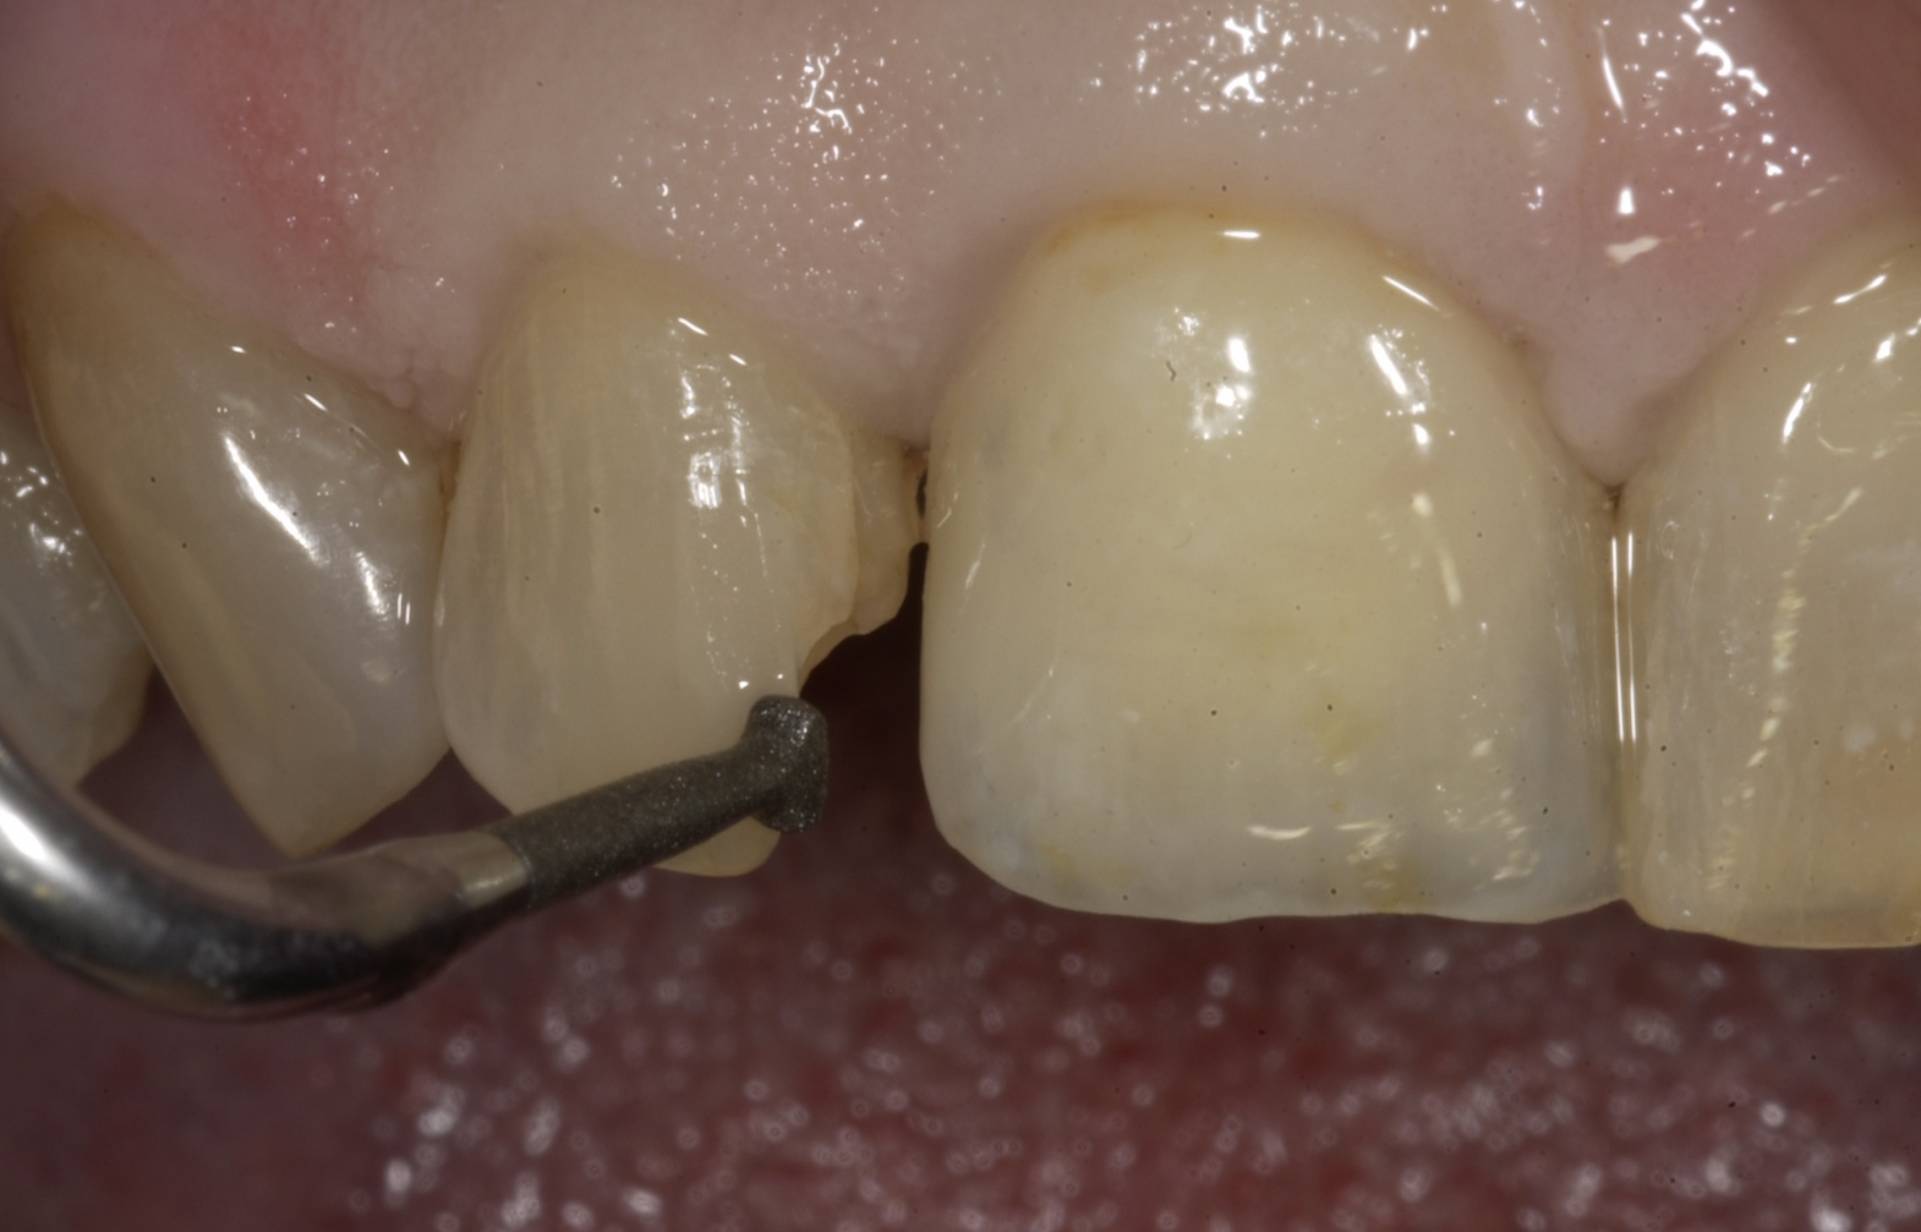

Mithilfe moderner Diagnostik, mikrochirurgischer Techniken und gewebeschonender Verfahren schaffen wir optimale Voraussetzungen für eine sichere Einheilung. Bei Bedarf werden knochenaufbauende Maßnahmen und biologische Regenerationskonzepte integriert, um auch in anspruchsvollen Situationen stabile Ergebnisse zu erzielen.